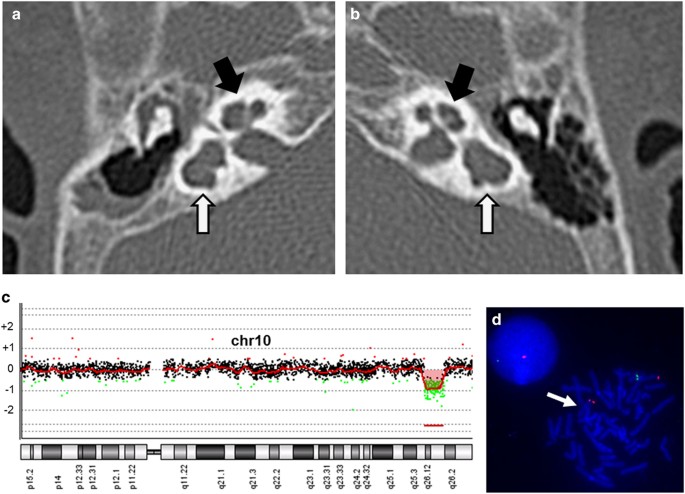

A 22-month-old Japanese girl was born to healthy and non-consanguineous parents following in vitro fertilization and gestation. She was born with a standard stature. Her family history was not remarkable. Patent ductus arteriosus was identified in the patient, and, soon after, it was surgically repaired. She exhibited a mild motor developmental delay: crawling at 12 months and walking alone at 20 months. Congenital deafness at a level of 50–60 dB was confirmed, and a hearing aid was required. A computed tomography scan of the temporal bone was performed, and bilateral middle ear hypoplasia was identified (Figures 1a,b).

The results of the radiological and genetic examinations. Computed tomography scans focused on the middle ears (a; right side, b; left side) show that bilateral lateral semicircular canals are dilated, shortened and non-circular (white arrows). Bilateral anterior superior semicircular canals and bilateral posterior semicircular canals are hypoplastic (black arrows). Hypoplastic findings are extreme on the right side. (c) Loss of genomic copy number involving 10q26.11q16.13 is shown using Chromosome View by Agilent Genomic Workbench (Agilent Technologies). (d) A 10q26.11q16.13 microdeletion is confirmed by fluorescence in situ hybridization (FISH). Red signals represent markers of 10p15.3 labeled on RP11–387K19, and green signals are targets of 10q26.13 labeled on RP11–57J8. A loss of the green signal (a white arrow) indicates a deletion of this region.

The study was performed in accordance with the principles outlined in the Declaration of Helsinki and was approved by the ethics committee of Tokyo Women’s Medical University. Blood samples were obtained from the patient and her parents after receiving written informed consent. Chromosomal microarray testing using the Agilent 60 K Human Genome CGH Microarray platform (Agilent Technologies, Santa Clara, CA, USA) was performed in accordance with previous descriptions of the method.8 A genomic copy number loss of 10q26.11q26.13 was identified in the patient. The molecular karyotype was arr 10q26.11q26.13(120,807,022–126,581,953)×1 (Figure 1c), indicating a 5.8-Mb deletion. Fluorescence in situ hybridization (FISH) analysis, using the bacterial artificial chromosome RP11–57J8 as a target probe, confirmed the deletion on the homologous chromosome 10q26.13 (Figure 1d). Parental FISH analysis showed no abnormality, determining a de novo occurrence in the patient. In this study, genomic positions were referred to as GRCh37/hg19.